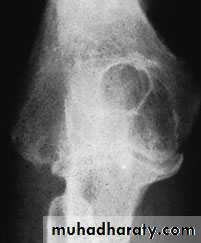

CUBITUS VALGUS

The normal carrying angle of the elbow is 5–15 degrees of valgus, anything more than this is regarded as a valgus deformitycommonest cause is longstanding non-union of a fractured lateral condyle

marked prominence of the medial condylar outline

The importance of cubitus valgus is the liability to delayed ulnar palsy